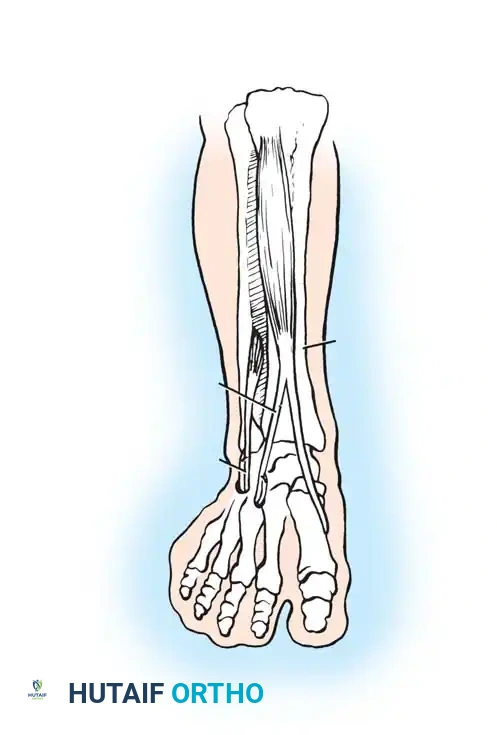

Surgical Technique: Achilles Lengthening and SPLATT Procedure

When dynamic EMG confirms that the tibialis anterior is firing continuously or inappropriately during the stance phase, causing the foot to supinate and invert, a Split Anterior Tibial Tendon Transfer (SPLATT) combined with Achilles lengthening is highly effective.

- Achilles Lengthening: Depending on the severity of the contracture, either a percutaneous Hoke triple hemisection or an open Z-lengthening of the Achilles tendon is performed to restore neutral ankle dorsiflexion. Care must be taken not to over-lengthen, which would result in a devastating calcaneal gait and profound weakness.

- SPLATT Incisions:

- Incision 1: Made over the insertion of the tibialis anterior at the medial cuneiform and base of the first metatarsal.

- Incision 2: Made over the anterior distal third of the leg, at the musculotendinous junction of the tibialis anterior.

- Incision 3: Made over the lateral midfoot, typically targeting the cuboid or the base of the third/fourth metatarsal.

- Tendon Splitting and Routing: The tibialis anterior tendon is split longitudinally from its insertion up to the musculotendinous junction. The lateral half of the split tendon is detached from its insertion, passed subcutaneously across the anterior ankle, and routed to the lateral midfoot incision.

- Fixation: The transferred lateral slip is anchored into the cuboid or lateral cuneiform using a biotenodesis screw or suture anchor, with the foot held in neutral dorsiflexion and slight eversion. This converts the deforming supinatory force of the tibialis anterior into a corrective, balanced dorsiflexion force.

- Postoperative Protocol: The patient is placed in a well-padded short leg cast in neutral alignment. Weight-bearing is strictly restricted for 6 weeks to allow for robust tendon-to-bone healing. Following cast removal, the patient transitions to a solid AFO and begins intensive physical therapy focusing on gait retraining and strengthening.

Surgical Warning: In the spastic patient, tendon transfers are rarely expected to function with normal voluntary, phasic control. Instead, they act as dynamic tenodeses. The primary goal of the SPLATT is to remove the deforming varus force and provide a balanced tether to maintain a plantigrade foot during the swing phase and initial contact.